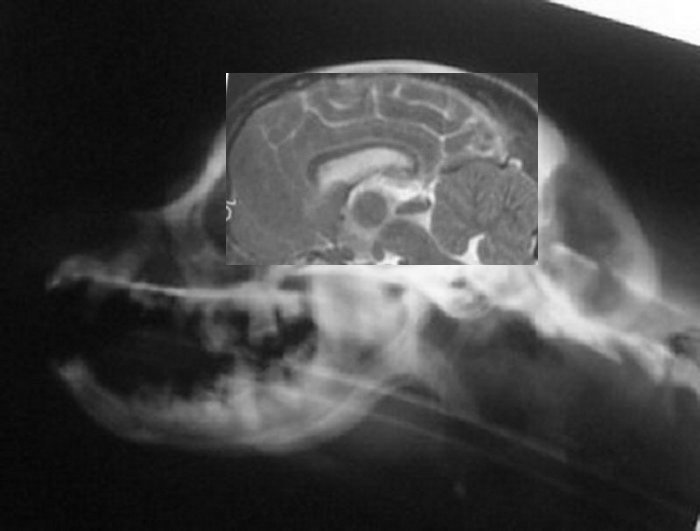

Below are more side skull x-rays of dogs who have also been MRId.

Their diagnosis will be listed below the comps. The idea is to

see if any differences in skull shape could be ascertained from

a simple skull x-ray. Next to it the MRI was fit into the skull

x-ray, just to see where everything fits in. Below is the

result. So far there appears to be a considerable difference in

the shape of the back of the skull between the dogs with SM and

without!

Dog above has moderate malformation and SM with symptoms